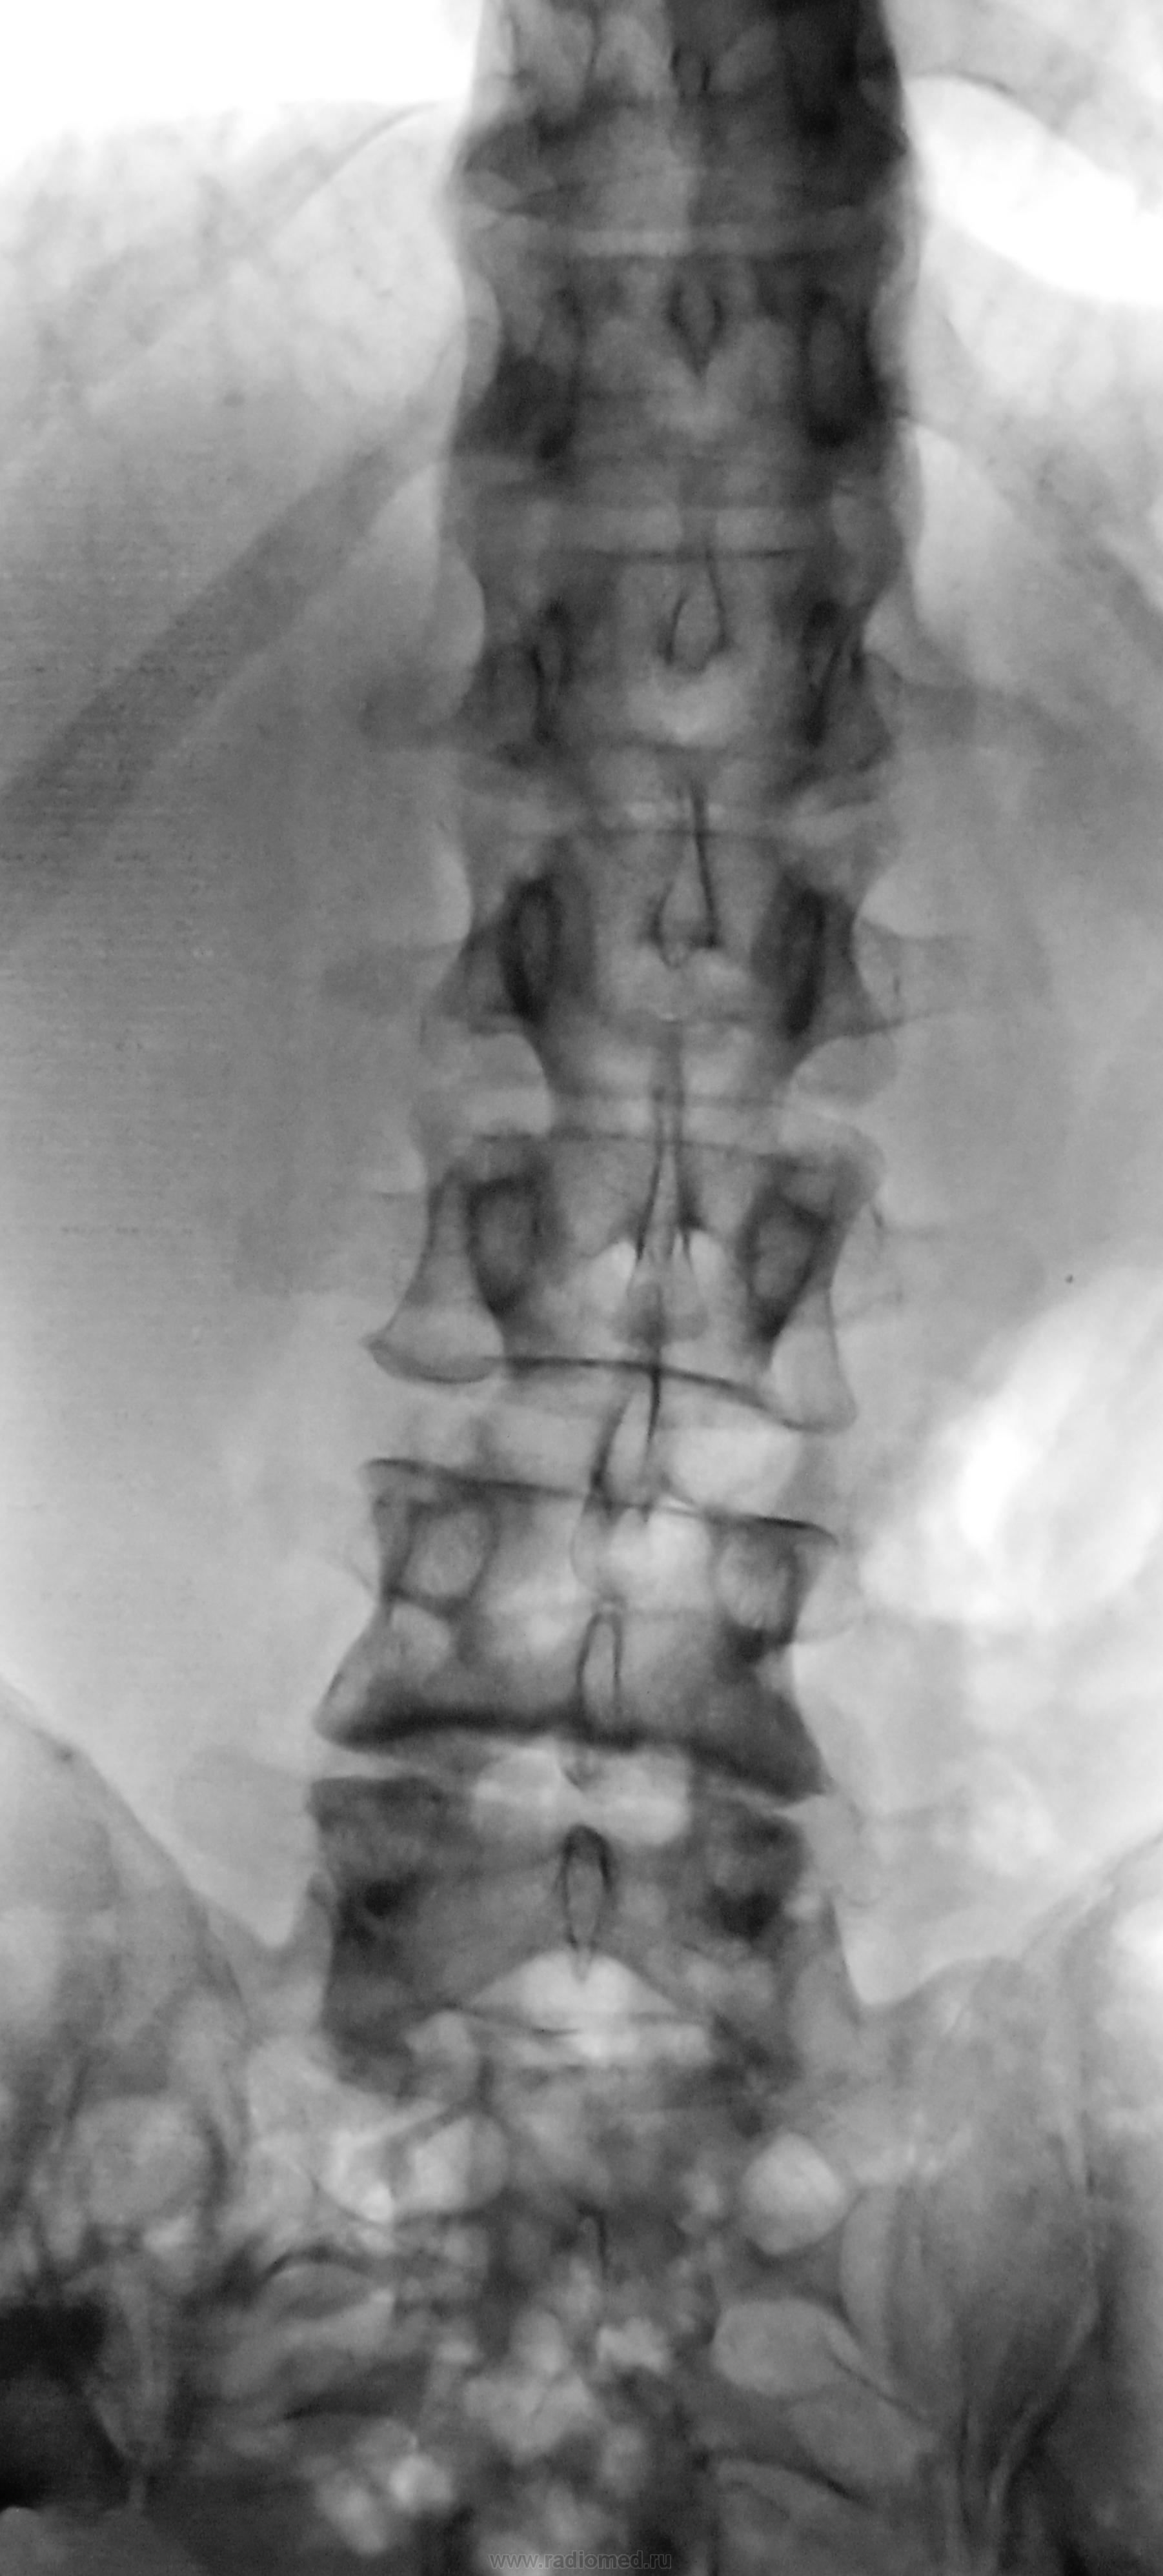

Я бы и листеза писать не стал: обычная задняя лестничная нестабильность L3,4,5, характерная для остеохондроза, преимущественное поражение МПД L4|5. Деформация м/п отверстий L3|4, L4|5.

Я бы и листеза писать не стал: обычная задняя лестничная нестабильность L3,4,5, характерная для остеохондроза.

Листез-это смещение, и оно тут есть. Термином "нестабильность" обычно пользуются при описании функциональных рентгенограмм.

Ok, кто проведет грань между листезом и нестабильностью без функциональных проб, но при наличии подобного (однонаправленного), но менее значимого смещения двух верхних позвонков. Давайте описывать листезы всех смещений на 1-2-3 мм.

Автору: понимая, что по сканограммам метрика не выйдет, запрашиваю величину смещения L5 в мм в данном наблюдении (?)

По поводу нестабильности на стандартных рентгенограммах. Следует ли любое малейшее смещение (может быть и кажущееся) описывать как нестабильность? Оправданно ли это? Или же все-таки термин нестабильность следует употреблять только по отношению к функциональным пробам? Например, по данному снимку можно ли говорить о наличии нестабильности сегментов позвоночника?

В таких случаях пишу ретролистез и рекомендую функциональные пробы.

Остеохондроз L4, L5, антелистез L5?

Не анте а ретро + грыжи Шморля

Ретролистез L5. Остеохондроз ПОП.